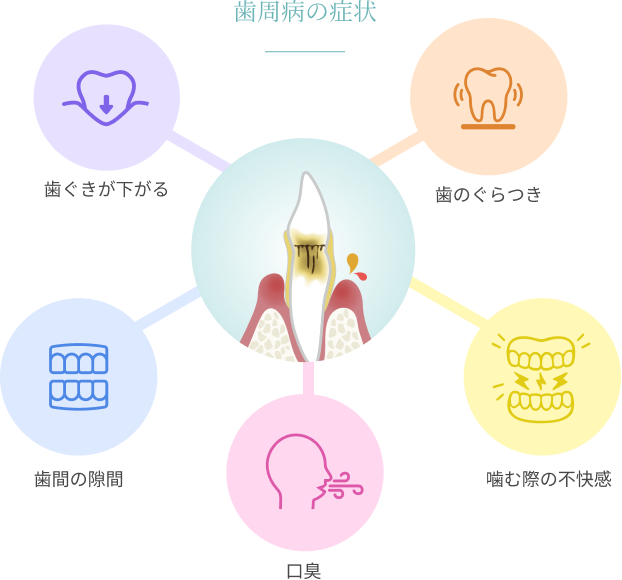

歯周病は、歯を支える歯ぐきや骨に炎症が起き、やがて支えを失って歯が抜け落ちる病気です。

初期段階では「歯ぐきの腫れ」や「出血」といった軽い症状が現れますが、

進行すると以下のような状態になります。